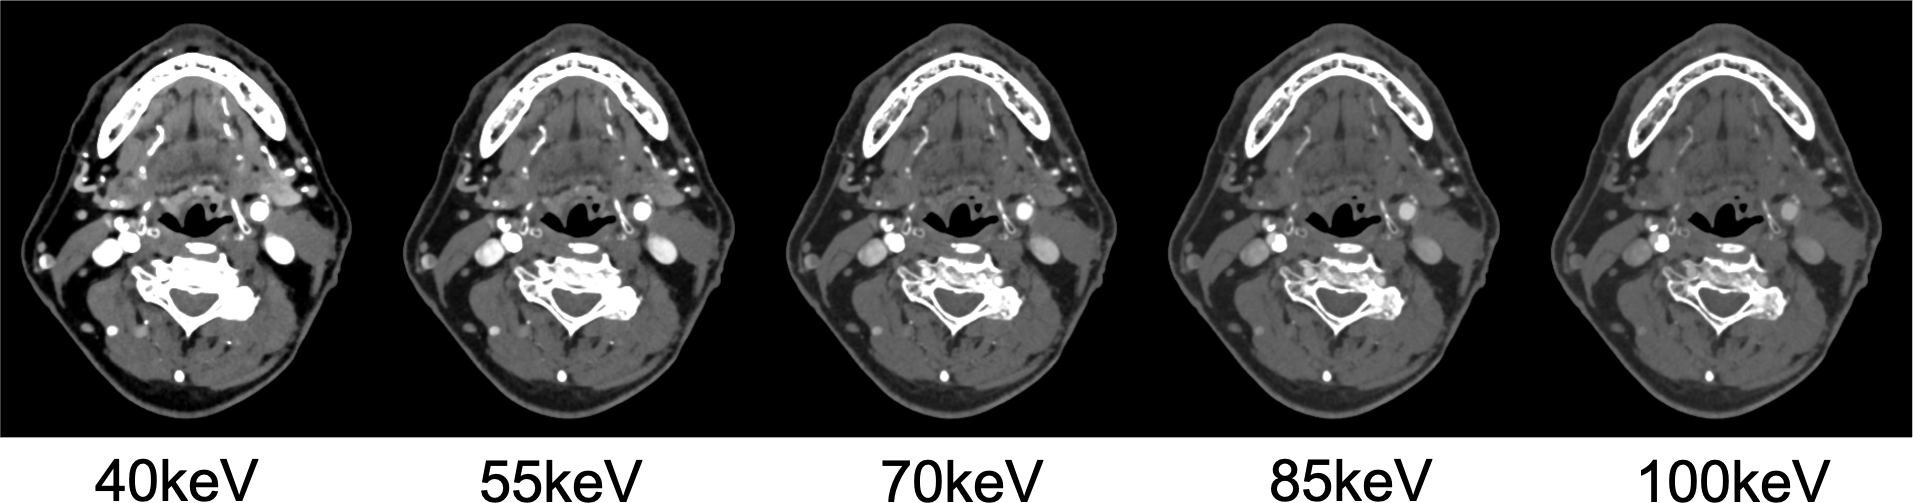

CT技術や撮像プロトコル設定について

Virtual Monoenergetic Imageで高エネルギー側の表示をすることで、金属アーチファクトを低減できたり、今回の症例のように、Iodine mapを用いることでヨード濃度を推定することができたり、Purelumen画像でCaなどの石灰化を除去することで、内腔の表示をより明瞭化する技術がある。シャープネスの高い動脈相の画像が望ましく、ヨード量は600mgI/kgは維持できるように気をつけている。